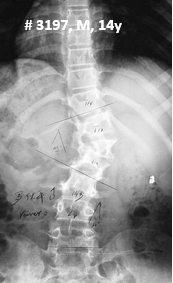

NF1患者脊柱在形态学上的异常主要包括椎体楔形变、椎体扇贝样改变(图6)、椎弓根狭窄(图7)、椎弓根间距增宽、横突纺锤形改变以及椎管扩大等。以上征象很少单独出现,往往合并存在。

图. 男性,14岁,X线下典型的椎体扇贝样改变